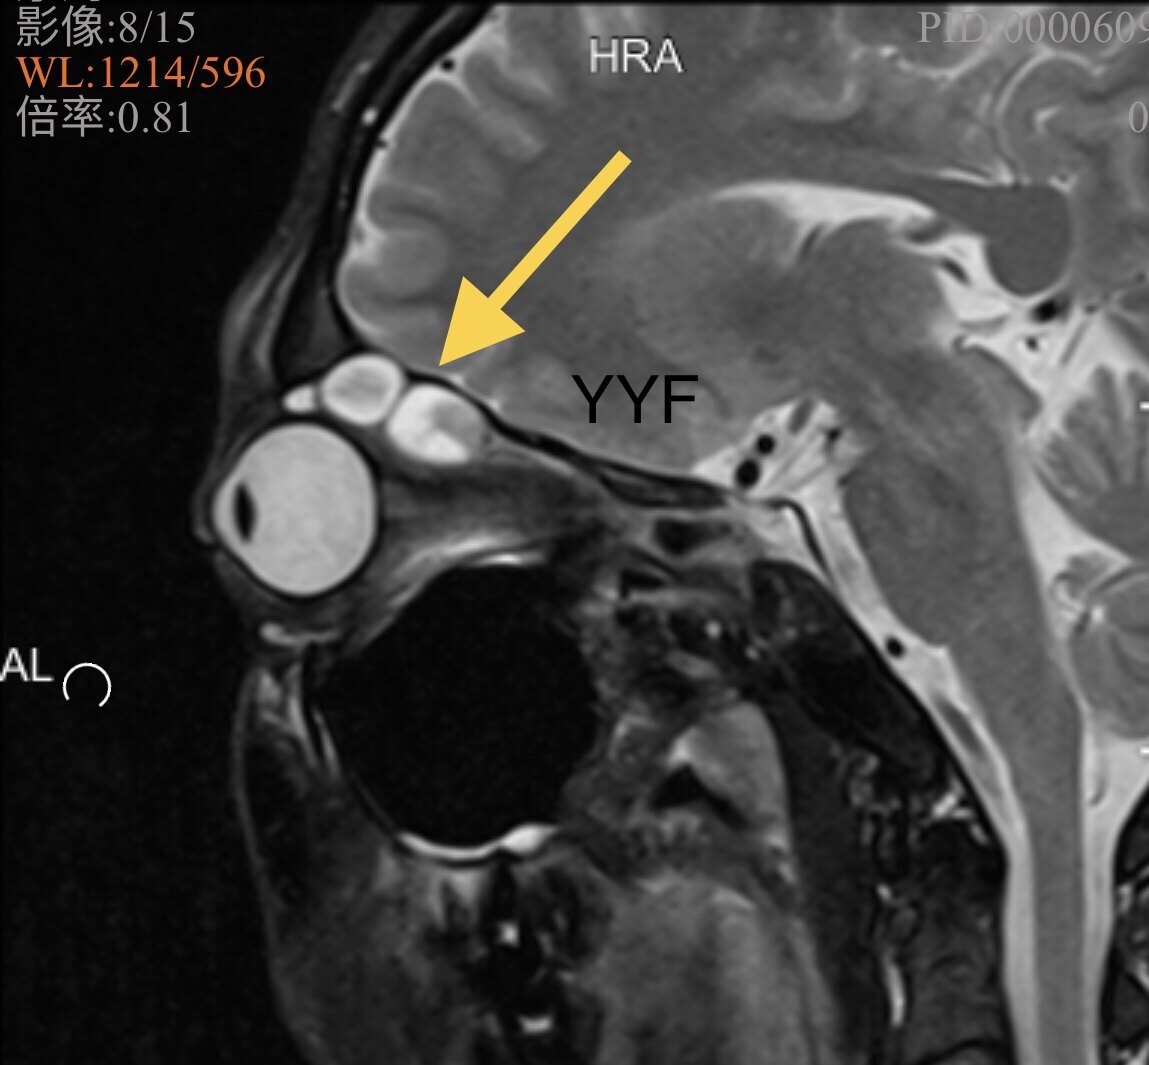

影像学显示肿物呈现不规则、结节状。

箭头处眶顶骨质压迫吸收

矢状位可以看到串珠样结节状外观及邻近结构的关系

T2加权表现有特征性